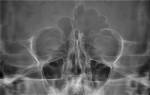

Чтобы понять, как выглядит гайморит на снимке, нужно знать, что воспалительные процессы и скопившиеся жидкости дают светлые контуры на темном фоне рентгенснимка.

В норме придаточные пазухи на рентгене не пневматизированы. На снимке здорового человека они определяются как темные образования по бокам носа, полуовальной формы. Чтобы определить, нормально или патологически окрашена область синуса, ее оттенок сравнивают с тенью глазницы. В норме цвет синуса и глазницы на рентгене совпадают.

Когда полость в ходе воспалительного процесса наполняется жидкостью, которая не имеет свободного оттока, на снимке появляется тень с горизонтальным уровнем.

На данном снимке можно четко разглядеть уровень жидкости в верхнечелюстных синусах. Этот эффект рентгенологи называют «молоко в стакане».

У пациента двусторонний гайморит. Для большей достоверности диагноза делается рентген в прямой и боковой проекциях. Если на двух полученных снимках визуализируется уровень скопившейся жидкости, диагноз гайморита не вызывает сомнений.

Определить же характер скопившейся жидкости – слизь это или гной – у рентгенолога нет возможности. При необходимости подробно исследовать все стенки верхнечелюстных пазух, делается рентген в трех проекциях – носоподбородочной, подбородочной и аксиальной.